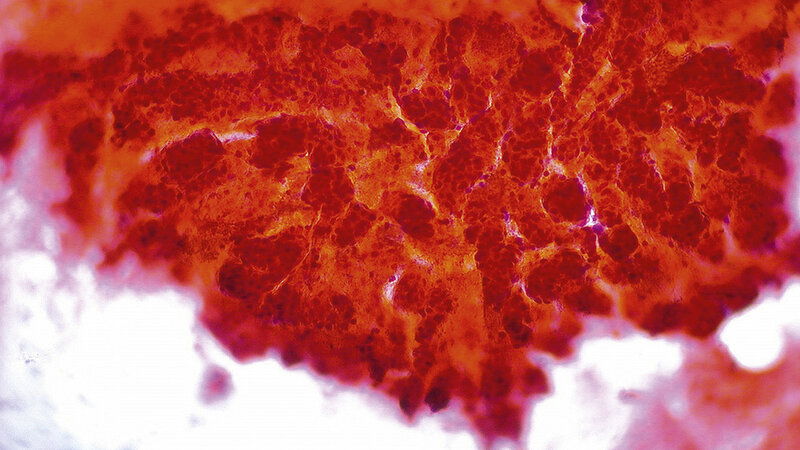

Für die Behandlung des hepatozellulären Karzinoms hat die selektive interne Radiotherapie (SIRT) in den letzten Jahren einen festen Stellenwert im Therapiekonzept erlangt. Aber auch für andere primäre oder sekundäre Tumoren der Leber stellt die SIRT eine wertvolle Option zur lokalen Behandlung dar. Bei sorgfältiger Patientenauswahl ist die SIRT eine komplikations- und nebenwirkungsarme Methode. Bedingt durch die physikalischen Eigenschaften von Yttrium 90 und der gezielten Applikation des Therapiestrahlers in den Tumor ist es möglich, im Tumor eine hohe therapeutisch wirksame Dosis zu erreichen. Weitere klinische Studien müssen nun zeigen, welchen Stellenwert die SIRT in Kombination mit anderen Therapieverfahren (zum Beispiel der Chemotherapie) besitzt beziehungsweise ob durch Therapiekombinationen weitere Überlebensvorteile für die Patienten erbracht werden können.